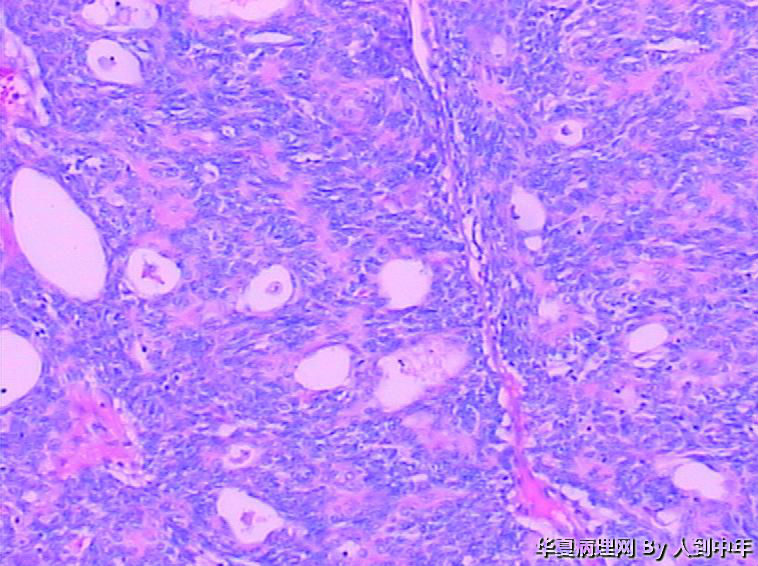

肺部肿瘤--类癌?求助大家

患者,男性,72岁,右肺中叶占位,肺门部肿物,散在多结节状,直径0.2-2.2cm。

• 肺部肿瘤--类癌?求助大家图1

图1

NT。需计数分裂像分级。

低分化癌,看到有腺样结构,肿瘤多结节,也要排除转移。

低分化癌,可能伴神经内分泌分化。不能标记也要建议会诊,去不去是他们的事

微囊、细胞梭形或立方、癌巢周边细胞见栅栏状(图22),不能排除基底细胞样癌。

癌,微囊、细胞梭形或立方、癌巢周边细胞见栅栏状,不能排除基底细胞样癌。多结节,也要排除转移性涎腺型恶性肿瘤,腺样囊腺癌等。